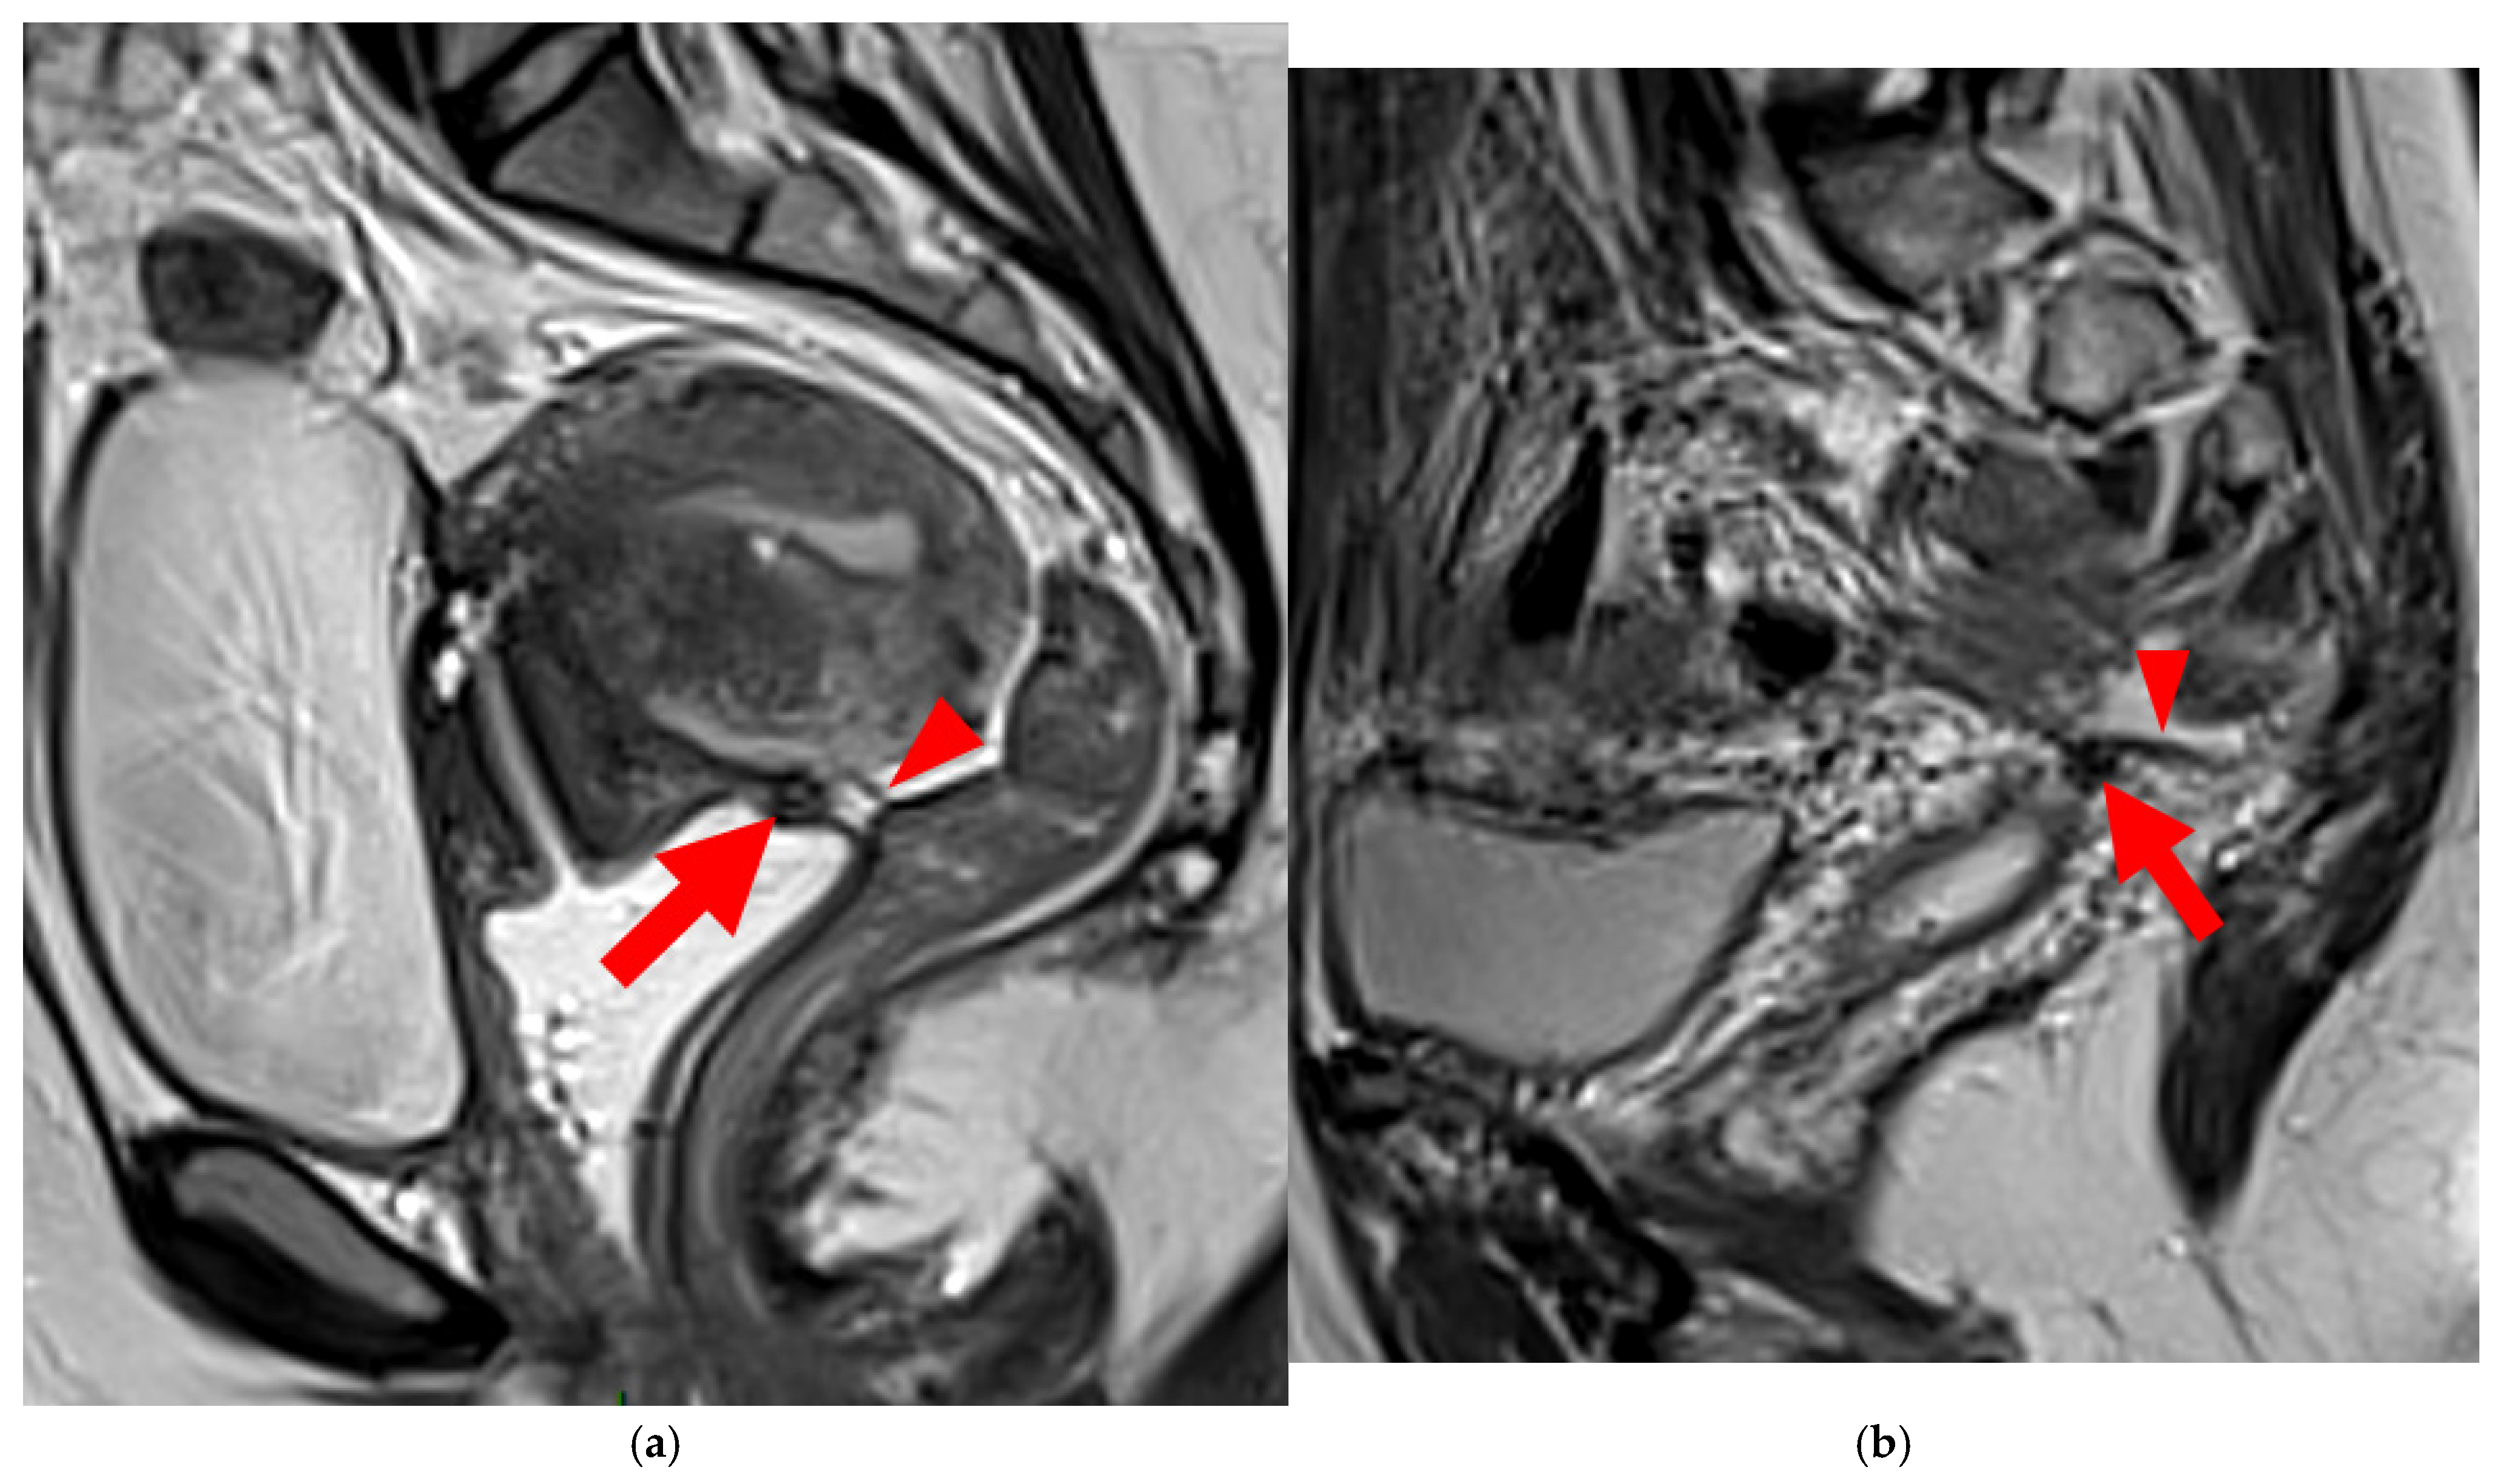

HTD Type 3B USL

A type 3B USL (Figure 4), in addition to being thickened, has a notched surface with slightly irregular margins, or a caliber disparity with focal thickening, or appears “stiffened”, which means it loses its curvilinearity to exhibit a steep vertical orientation in the sagittal plane or a “bowstringing” of the USL in the sagittal or axial planes. Occasionally, a USL might appear thin but “stiffened”, which would upgrade it from a type 2 to a type 3B.

Figure 4. Pelvic MRI scans of seven patients with HTD type 3B USLs. (a) Sagittal T2WI: a thickened (2.1 mm) and stiffened right USL (arrowhead) with “bowstringing”. (b) Axial T2WI: a caliber disparity (dashed arrows) with focal thickening (4.2 mm) of the left proximal USL (arrowhead). (c) Sagittal T2WI: a caliber disparity (dashed arrows) with focal thickening (2.5 mm) of the right distal USL. (d) Axial T2WI: a right USL with a notched and irregular surface (dashed arrows). (e) Axial T2WI: thickened and stiffened left (3 mm) and right (2.5 mm) USLs with “bowstringing” of both USLs (arrowheads). (f) Sagittal T2WI: a thickened (2.6 mm) right USL with a stiffened appearance characterized by a steep vertical orientation (arrowhead). (g) Sagittal T2WI: the right USL appears thin (1.9 mm) but stiffened (arrowhead), exhibiting “bowstringing”. These findings led to its reclassification from type 2 to type 3B.